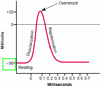

Qual valor é definido como o potencial de repouso das membranas das fibras nervosas mais calibrosas?

-90 mV.

O potencial de repouso é quando não há…

transmissão de sinais nervosos.

(-90mV)

Fisiologia: Sistema Nervoso

O potencial de repouso significa que o potencial _____ (dentro/fora) da fibra é 90 mV mais negativo do que o potencial no líquido ________ (intracelular/extracelular).

Dentro; extracelular.